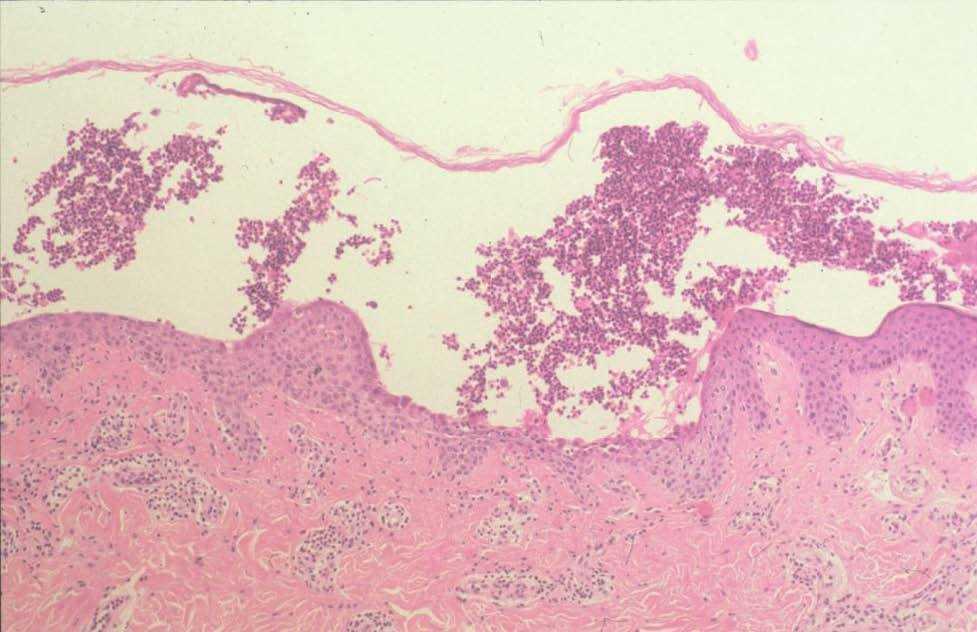

El estudio histológico de las lesiones cutáneas mostró una pústula subcórnea con abundantes neutrófilos en su interior y algunos queratinocitos acantolíticos en el suelo de la misma (fig. 2). Mediante inmunofluorescencia directa (IFD) se demostró depósito de inmunoglobulina G (IgG) en la superficie de los queratinocitos. La inmunofluorescencia indirecta (IFI) fue negativa.

Fig. 2.—Pústula intraepidérmica que contiene numerosos eosinófilos y algunas células acantolíticas. (Hematoxilina-eosina, ×20.)